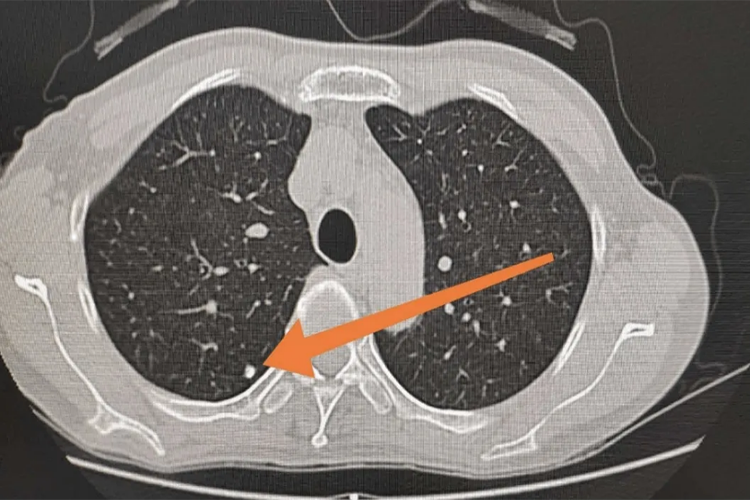

2、混合磨玻璃肺部结节的形态特征:混合磨玻璃肺部结节在影像学上表现为密度不均、呈磨玻璃样的结节。这种结节的密度不均主要是由于构成磨玻璃结节的病灶中,既有细胞浸润,也有水分渗出。这种形态学特征是各种疾病在胸部影像学检查上的一种表现,但具体的病因可能相同,也可能不同。

4、混合磨玻璃肺部结节的诊断:混合磨玻璃肺部结节的诊断主要依赖于影像学检查,如X线或CT等。在诊断过程中,医生会根据结节的大小、边缘是否光滑、是否有毛刺、周边是否有胸膜凹陷等特征,结合患者的临床症状和病史,进行综合分析判断。对于疑似恶性病变的结节,可能需要进行进一步的检查,如病理活检等,以明确诊断。